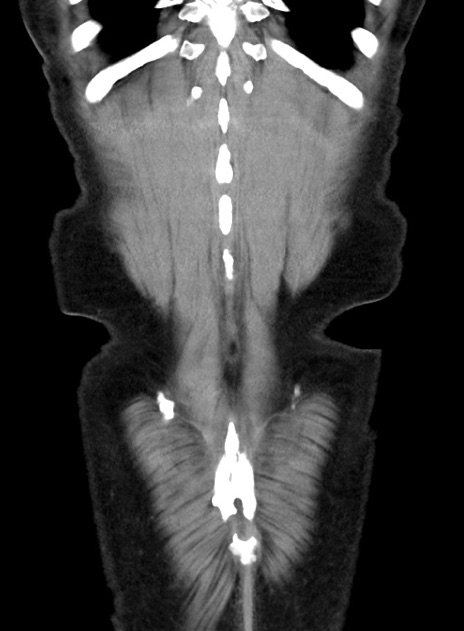

横断像

【症例】70歳代 男性

【主訴】腹痛・嘔吐

【現病歴】昨晩より、嘔吐・腹痛あり。今朝になっても嘔吐あり。来院。

【既往歴】心臓バイパス手術、開腹胆摘、腸閉塞

【身体所見】BP 107/71mmHg、HR 116/min、腹部:平坦、軟、下腹部に軽度圧痛あり。反跳痛なし。

【データ】WBC 15100、CRP 0.32